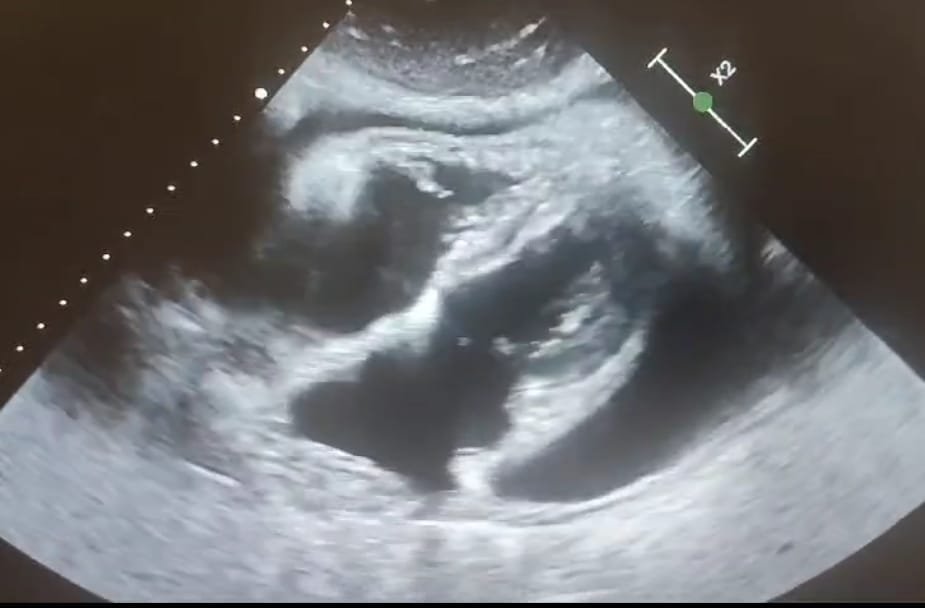

Le diagnostic de la péricardite repose sur l'examen clinique, où le médecin peut détecter un frottement péricardique à l'auscultation, caractéristique de cette affection. Des examens complémentaires sont également réalisés, tels que l'électrocardiogramme (ECG), qui peut montrer des anomalies spécifiques, et l'échocardiographie, qui permet de visualiser un éventuel épanchement péricardique. Des analyses sanguines peuvent aussi être effectuées pour identifier des marqueurs inflammatoires ou infectieux.